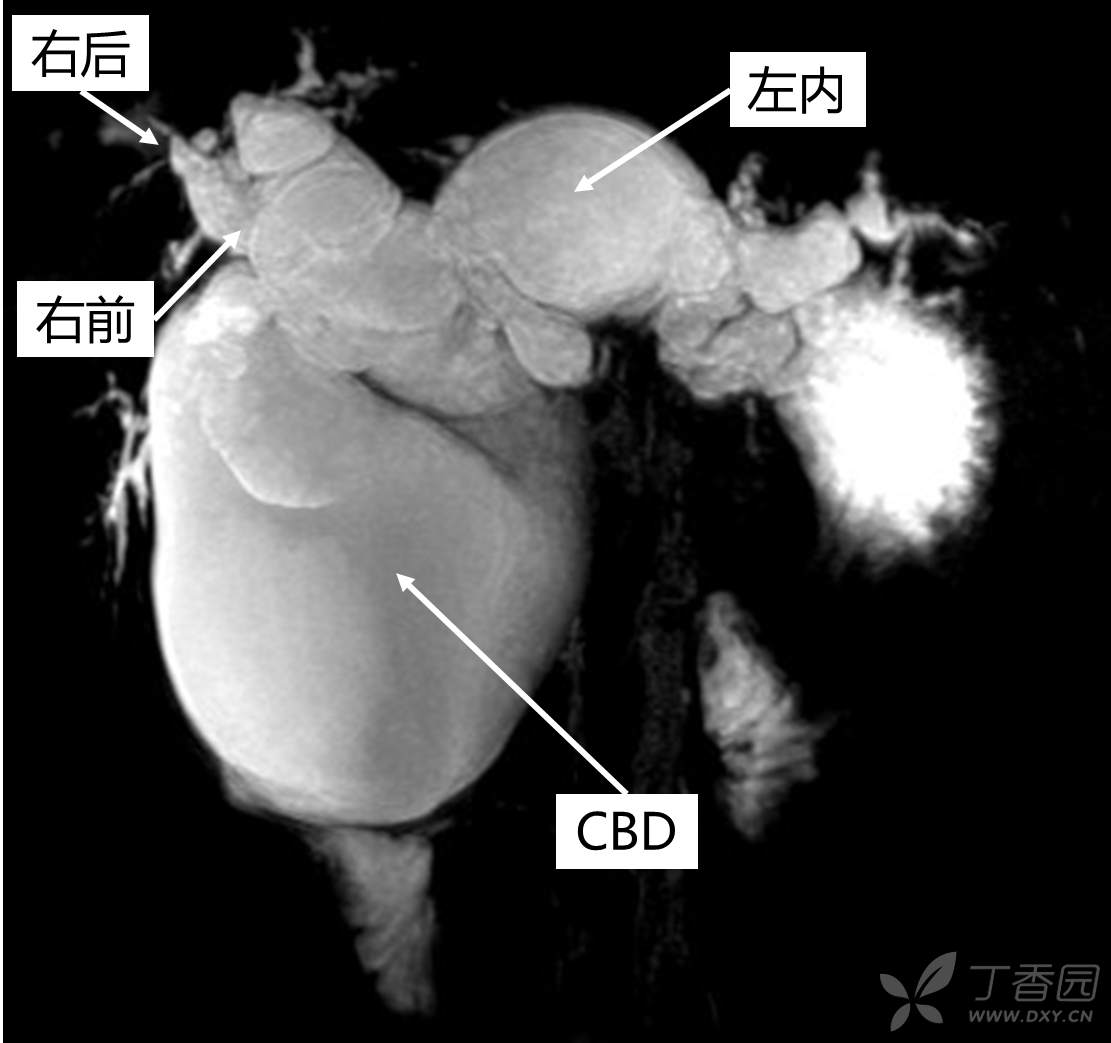

术前的仔细分析非常关键,这里的年轻医生都可以做的很好,如图标注:左内叶、右前叶的肝内胆管都扩张了,胆总管扩张严重一直达到胰腺实质内: